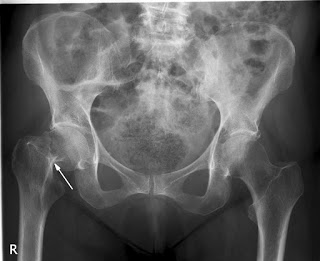

Cirugía de cadera ultrarrápida

02 marzo 2020

En pacientes con fractura de cadera, la cirugía en las primeras seis horas del diagnóstico no obtuvo mejores resultados que la realizada a las 24 hs del mismo. The Lancet, 29 de febrero de 2020.